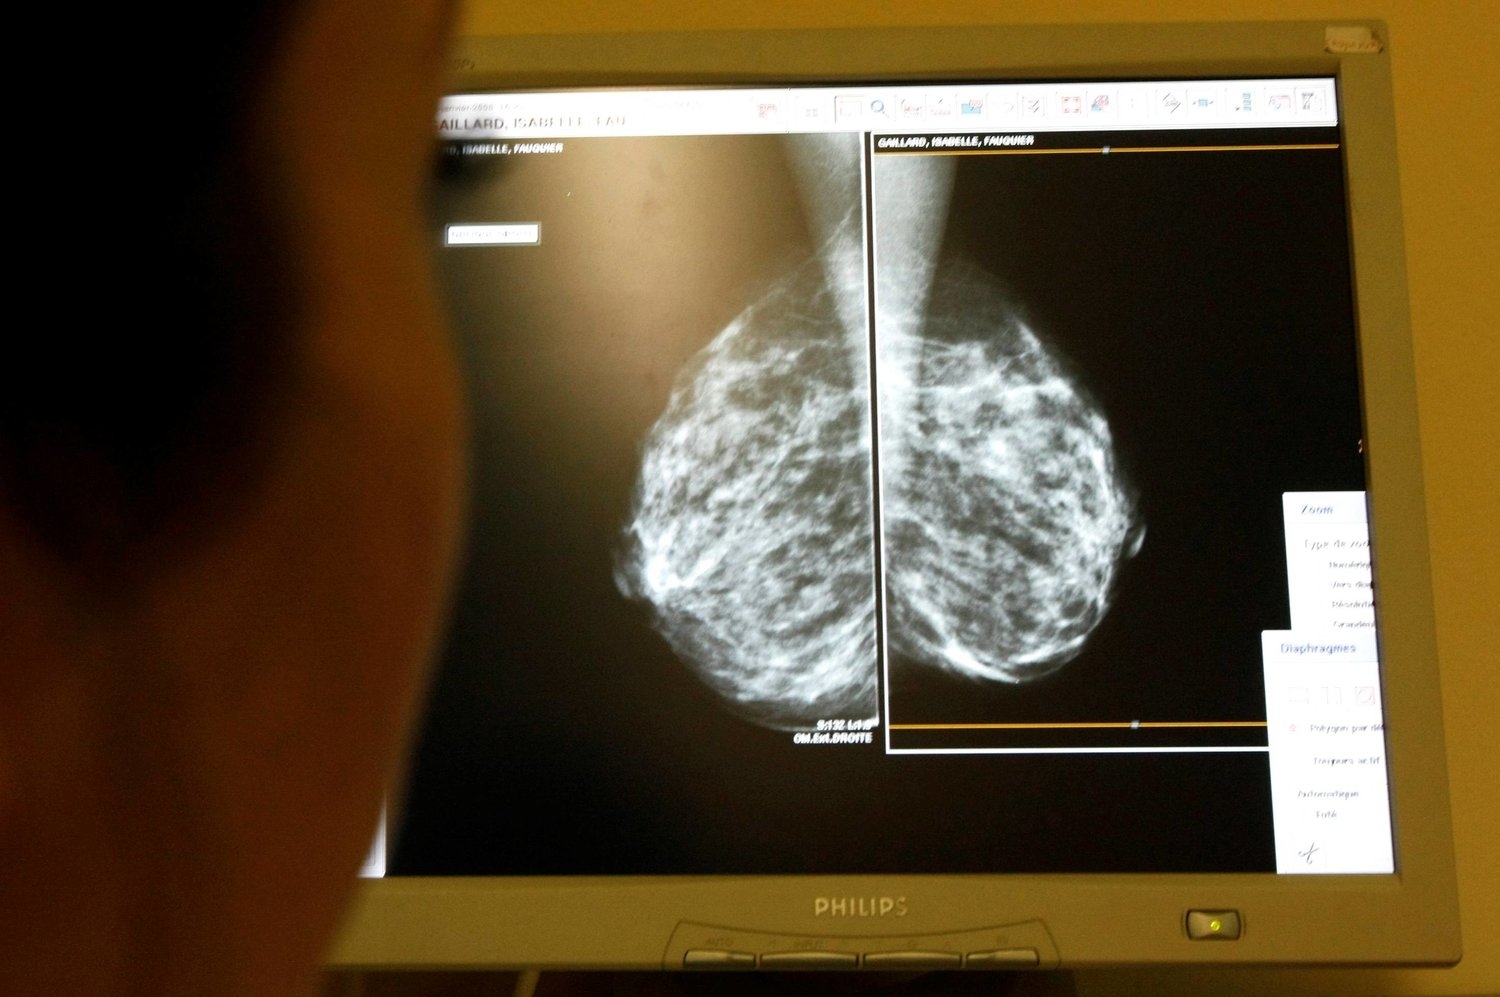

عقار تجريبي جديد يضعف سرطان الثدي العدواني

كشف باحثون بمركز لومباردي الشامل للسرطان بجامعة جورج تاون بالتعاون مع علماء بجامعة ميامي بفلوريدا عن عقار تجريبي جديد أطلق عليه TTP488 (azeliragon) يضعف سرطان الثدي العدواني الثلاثي السلبي الناتج عن انتشار النقائل على المستوى الخلوي.

ونشر الاكتشاف الجديد يوم (الخميس) الماضي بمجلة Nature Breast Cancer. وتمثل سرطانات الثدي ثلاثية السلبية (TNBCs) حوالى 10-15 % من جميع حالات سرطان الثدي المشخصة؛ وتتكون من خلايا سرطانية لا تحتوي على مستقبلات هرمون الاستروجين أو البروجسترون، ولا تنتج بروتينًا يسمى «HER2» بكميات كبيرة. فيما تعتبر TNBC أكثر شيوعًا عند النساء الأصغر من 40 عامًا أو النساء السوداوات؛ بالنسبة لتلك السرطانات التي تنتشر، فإن معدل البقاء على قيد الحياة لمدة خمس سنوات هو 12 % فقط.